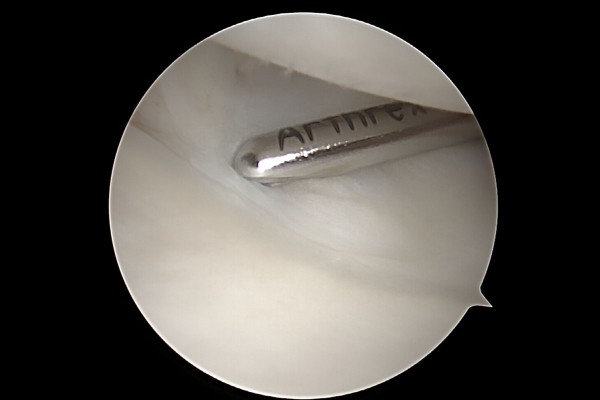

e2dae621a1572a5ea8be78c4dc6d0de9_1768291790_33.jpg

이를 절삭기구(Shaver)를 이용하여 제거해줍니다.